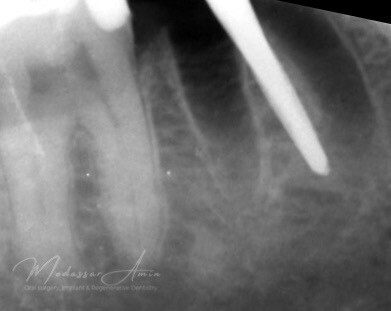

"Pasienten presenterte med tann 46 som ikke kunne bevares grunnet en dyptgående infraksjon inn i furkasjonen. Forholdene lå til rette for en immediate implantatbehandling. Ved hjelp av Versah osseodensifikasjonsbor ble det interradikulære beinet ekspandert på en skånsom og forutsigbar måte, noe som ga høy primærstabilitet (>40 Ncm) til tross for en lokal bendefekt apikalt mesialt etter kronisk apikal periodontitt. Den gode stabiliteten muliggjorde bruk av SSA (Sealing Socket Abutment) for forsegling. På grunn av tynn bløtvevsfenotype bukkalt ble behandlingen supplert med bindevevstransplantat (CTG)"

Kontrollröntgen implantat

Kontrollröntgen SSA